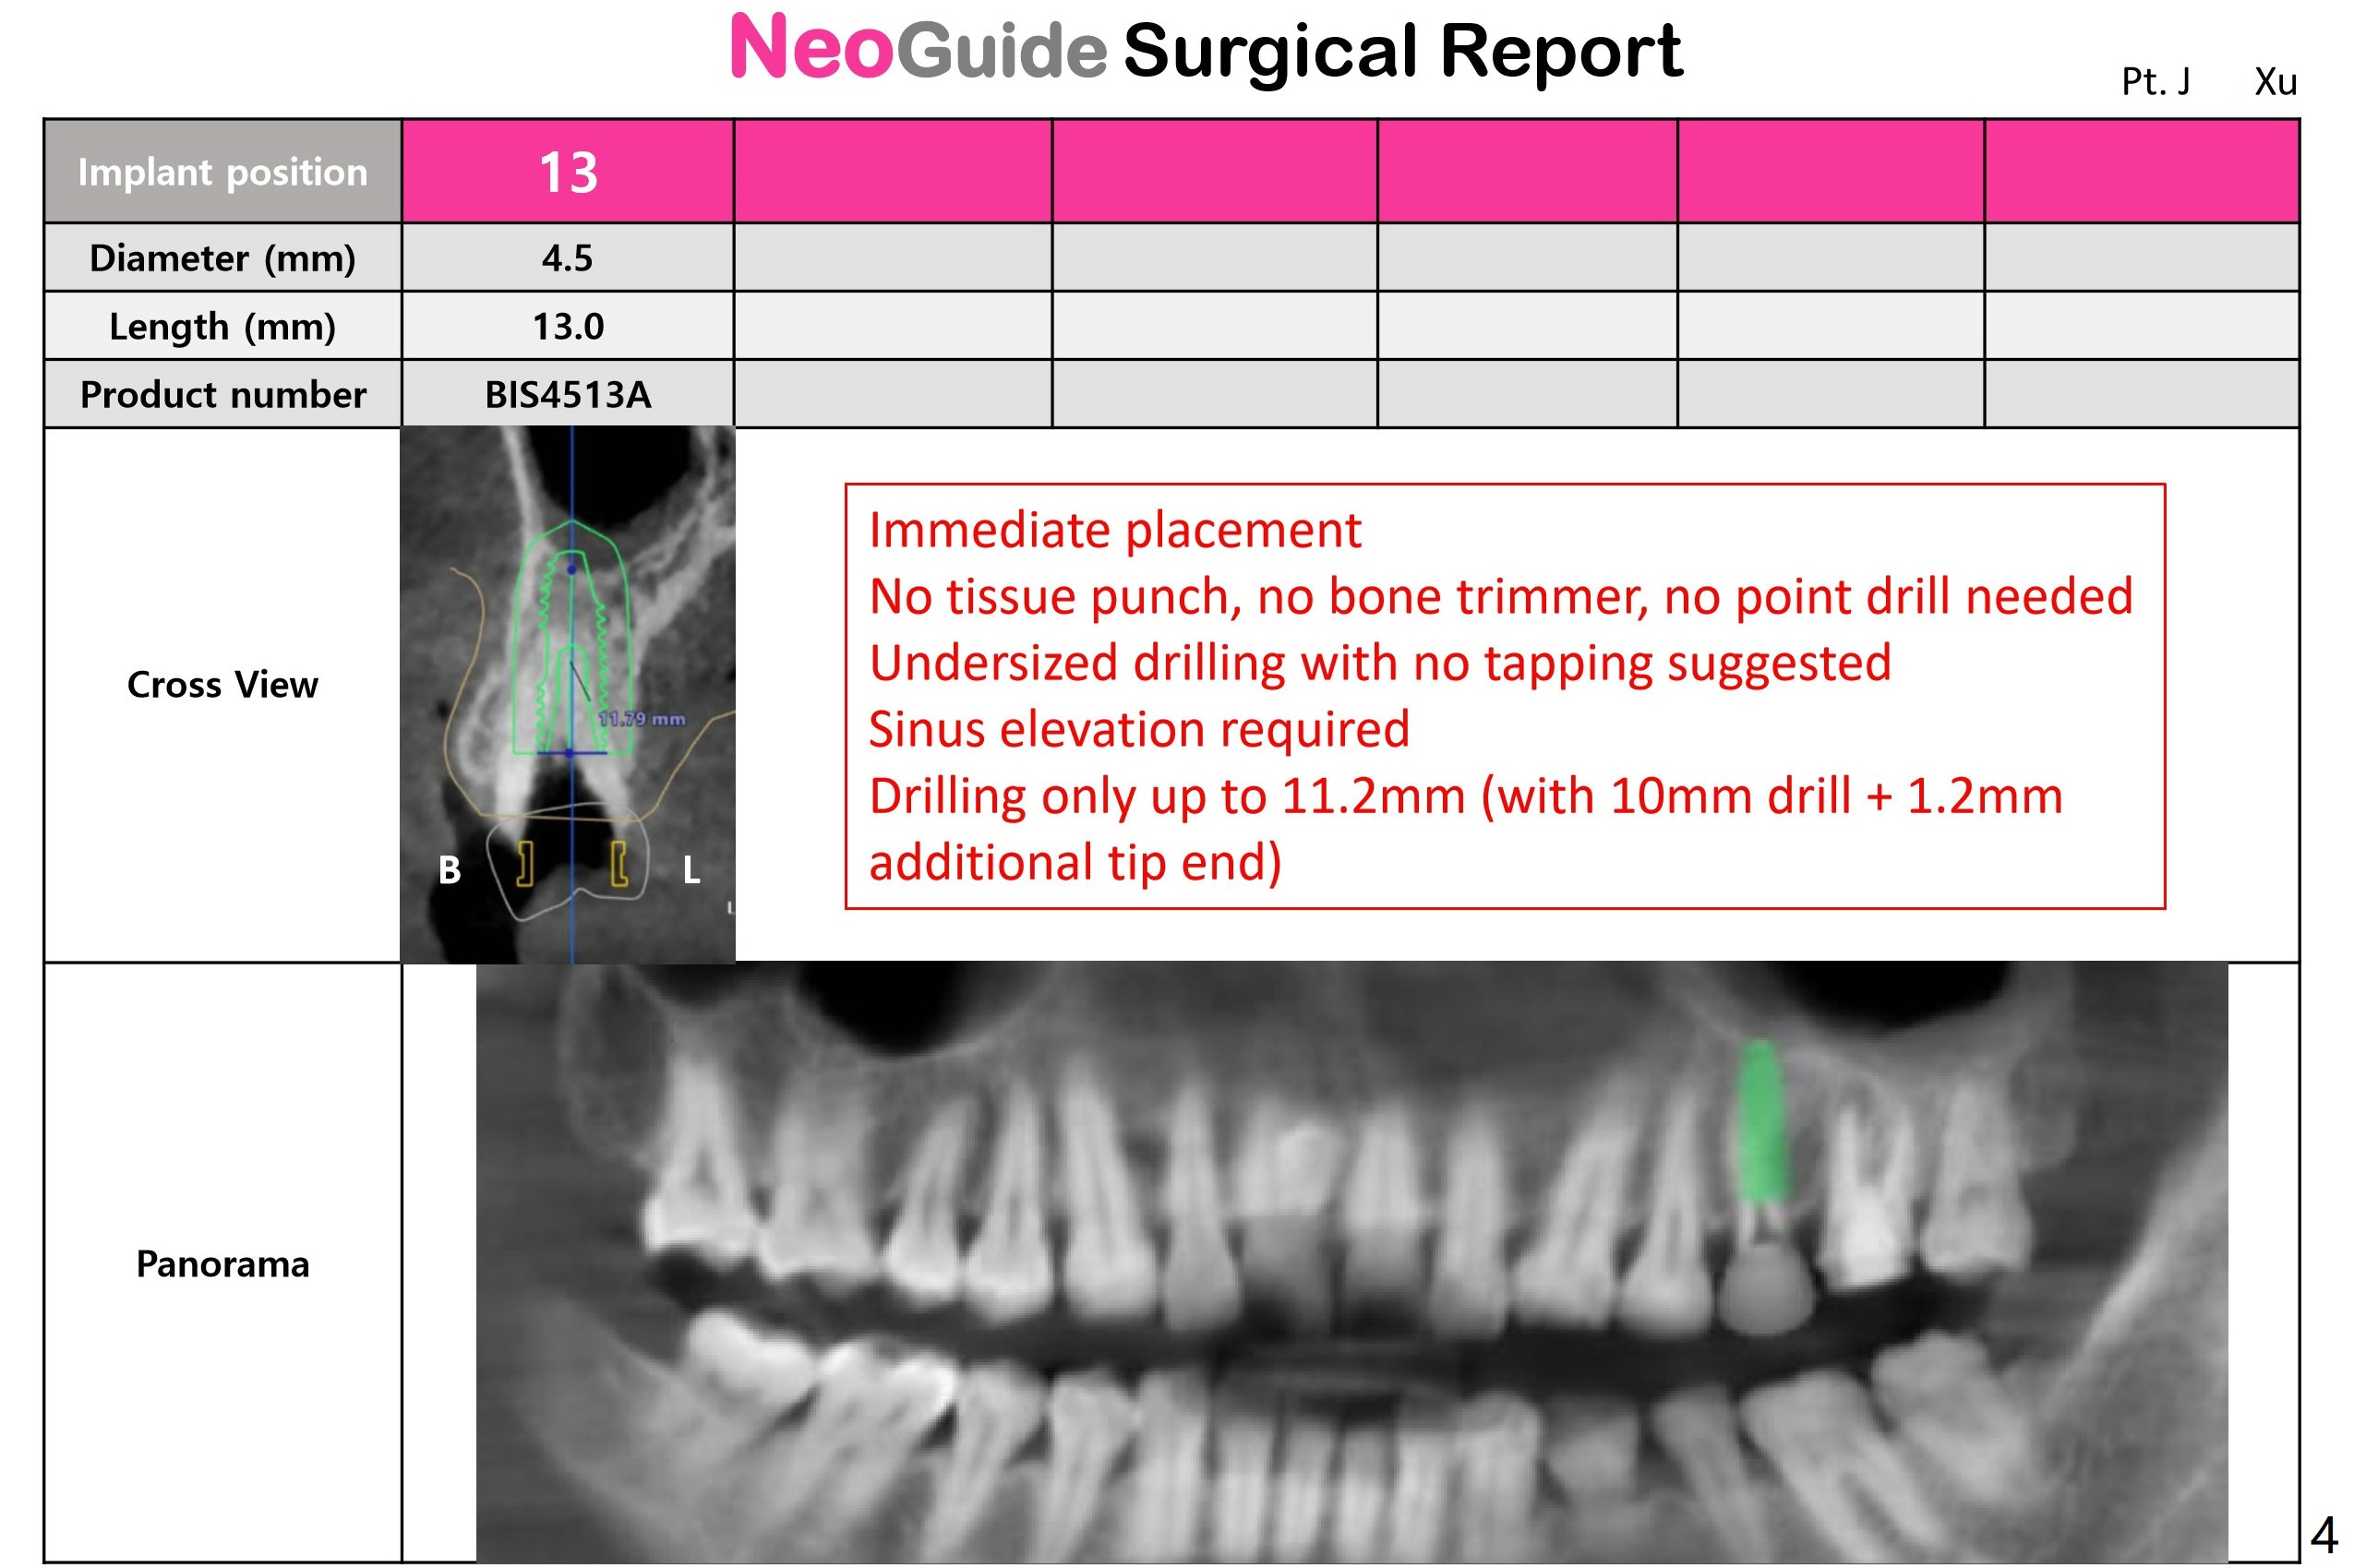

Underprep in Depth for Sinus Lift

After #13 implant placement, remove DO caries at #14 for composite and splinted provisional. Consider taking PA after 2.2 mm drill to depth because of the curved root of #12. Placee IBS implant with IS driver.

Return to Upper Premolar Immediate Implant, Trajectory II Clindamycin